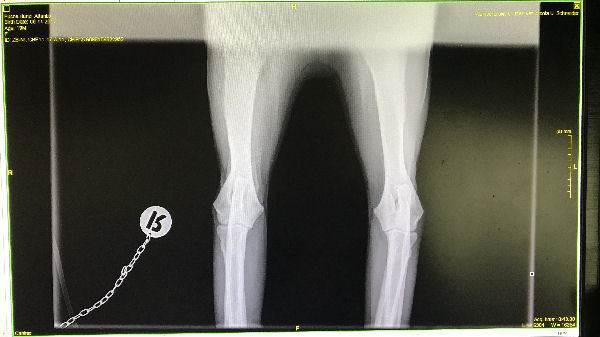

Atlantis - ED-Röntgen

img_5245-Atlantis-ocd